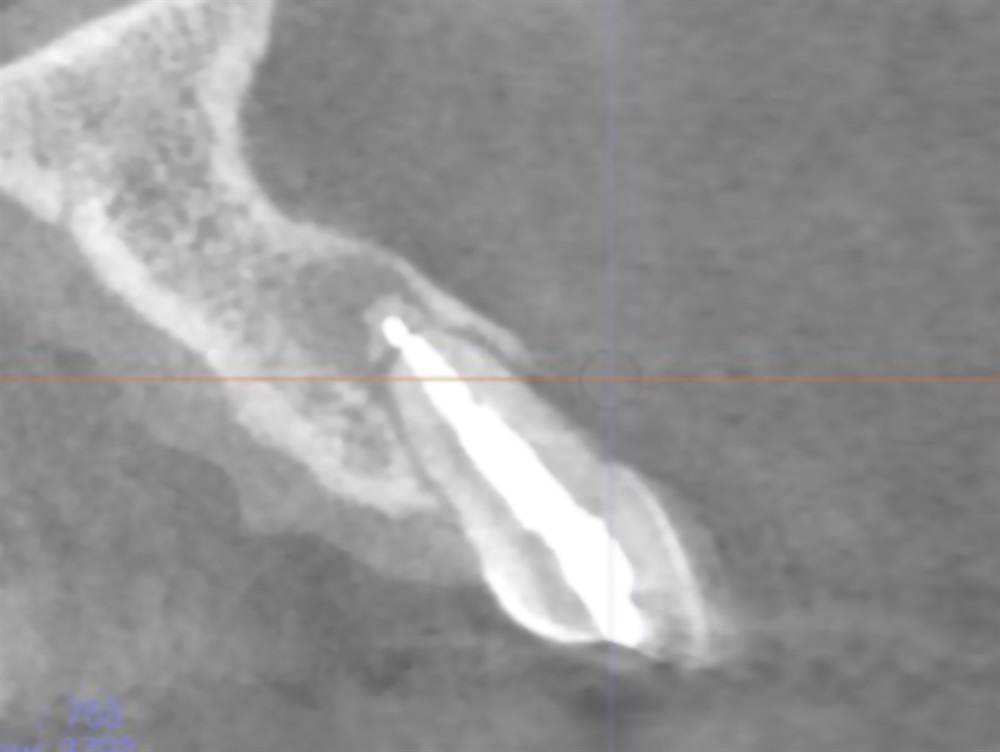

As part of my graduate program, I’m participating in a randomized controlled clinical trial that compares different membranes in extraction and preservation procedures. One of my faculty members is the principal investigator, and multiple residents work on different data sets. I’ll be studying hard tissues, measuring CT scans and bones before and after healing, to see if there is a difference in that hard-tissue volume maintenance between the two treatment modalities. (Essentially, trying to determine which membrane, if any, works better in preserving the bone for a future implant.)

This remains one of my favorite cases because it really displays the success one can have with anterior implant cases. I was using a modified “dual zone therapy” technique (developed by Drs. D.P. Tarnow and S.J. Chu), which I have found to have great utility in an office where making immediate provisionals does not fit the workflow.

Horton Favorite Case